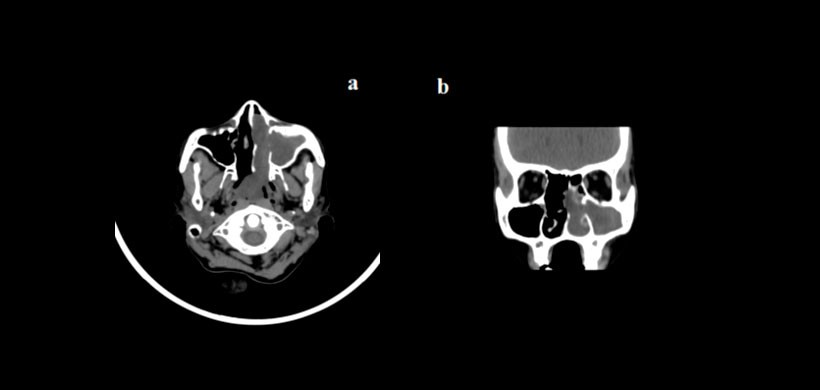

Los senos nasales y paranasales son el anfitrión de un amplio espectro de enfermedades y afecciones que pueden denominarse colectivamente como enfermedades nasosinusales. Las patologías sinonasales incluyen amplio espectro de condiciones que van desde inflamatorios a neoplasias, tanto benignos como malignos (Figura 1 y Figura 2). La evaluación radiológica de las enfermedades sinonasales es muy esencial ya que los hallazgos clínicos en estos casos pueden ser no específicos. Las técnicas de imagen disponibles incluyen radiografía simple, CT, resonancia magnética (MRI) y tomografía de emisión de positrones (PET).

La TC se ha convertido en la investigación de elección para el diagnóstico radiológico de las enfermedades nasales y de los senos, ya que las imágenes de TC muestran claramente el aire, opacificaciones sinusales y la estructura fina de la anatomía ósea. El TC multidetector (MDCT) permite la evaluación de la permeabilidad de los pasajes sinonasales y muestra el efecto de variantes anatómicas, enfermedad inflamatoria o ambas en la permeabilidad. MDCT puede mostrar estructuras anatómicas que no se visualizan por examen físico o endoscópico y es, por lo tanto, el estudio de elección para el cirujano.

La TC también desempeña un papel importante en la exclusión de la existencia de infecciones agresivas o neoplasias con características de extensión extra sinusal, destrucción ósea e invasión local. La RM se puede realizar en casos de complicaciones de sinusitis, extensión extra sinusal de malignidad y para evaluar la extensión intracraneal. La TC es superior a la RM en la evaluación de detalles óseos finos, lesiones fibro-óseas de SNP y traumatismo sinofacial.